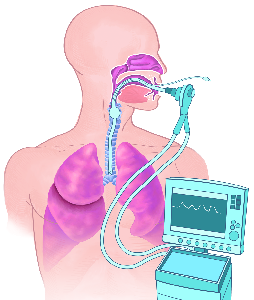

Detailreiche Fotografien aus der medizinischen Praxis ergänzen die Texte; moderne, genaue,

wissenschaftliche Zeichnungen geben Einblick in die Anatomie und die Funktion der Lunge und

anderer Organe.